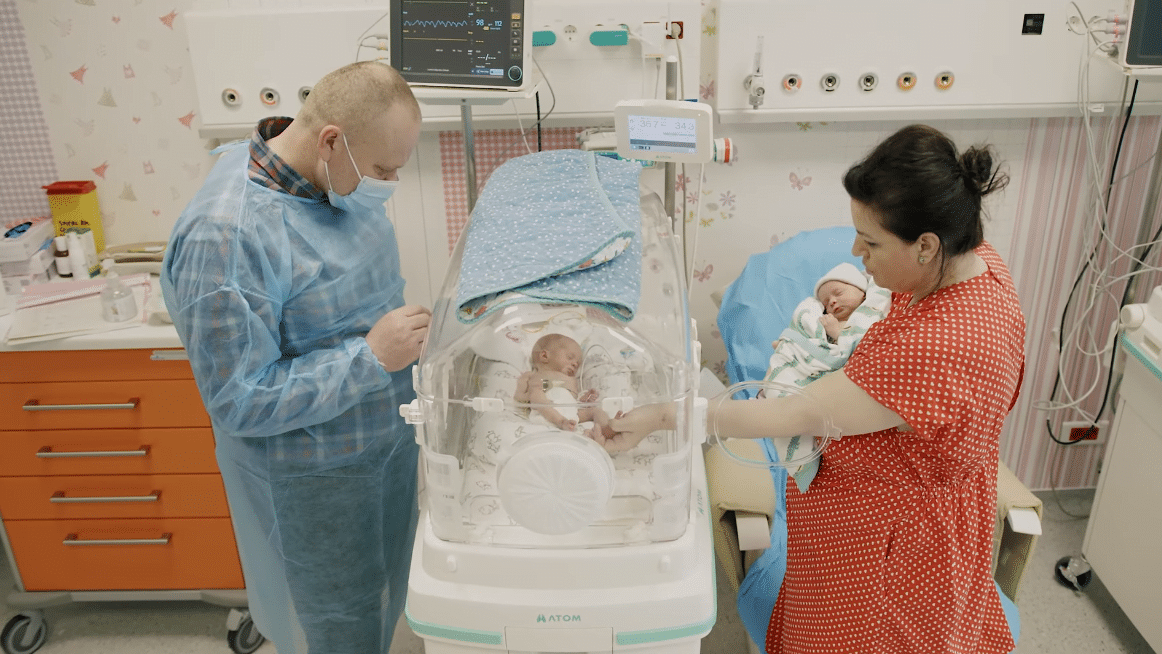

Corina a născut două fetițe gemene univiteline, obținute prin FIV. Cele două fetițe au venit pe lume prematur la 36 de săptămâni de sarcină, însă au depășit prematuritatea fără niciun fel de probleme. Micuțele au fost îngrijite în secția de terapie neonatală a Spitalului Regina Maria din Cluj.

Dr. Sorin Andreica, Medic primar Neonatologie: „În secția de Terapie Intensivă Neonatală, cei mai mulți copii sunt născuți înainte de termen, deci copii prematuri. Prin urmare, echipamentele, infrastructura, personalul medical este pregătit pentru a primi astfel de copii prematuri. În momentul de față îngrijim copii născuți de la 32 de săptămâni de gestație. Confortul de îngrijire este cât se poate de bun atât pentru copil, cât și pentru părinți. Inclusiv tatăl poate să participe la aceste îngrijiri, prin urmare întreaga familie poate să fie implicată în îngrijirea unui copil înainte de termen.”